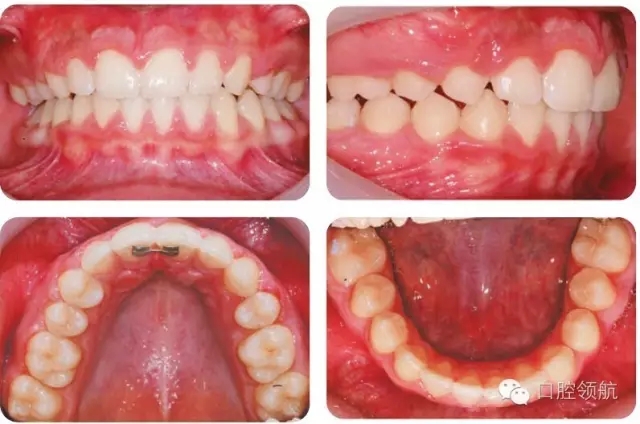

UR4應如何改形模擬UR3?

UR4改形受到休息和功能狀態(tài)時上唇位置和上前牙外觀影響。休息時上唇線較低,切緣暴露很少,這樣齦緣高度不一致的情況不必特別考慮。因為第一前磨牙近遠中徑小于尖牙,托槽應略靠遠中使牙齒近中腭側(cè)旋轉(zhuǎn)。為了使前磨牙伸長,托槽應放置在臨床牙冠中心略偏齦方,使頰尖位置與對側(cè)尖牙協(xié)調(diào)。如果伸長前磨牙導致咬合早接觸,應適當降低舌尖。如果笑線較高,應考慮壓入第一前磨牙或外科修整齦緣高度。前磨牙可以進行貼面以更好地模擬尖牙外觀,調(diào)整牙尖垂直位置。圖2.45為最后的咬合像。